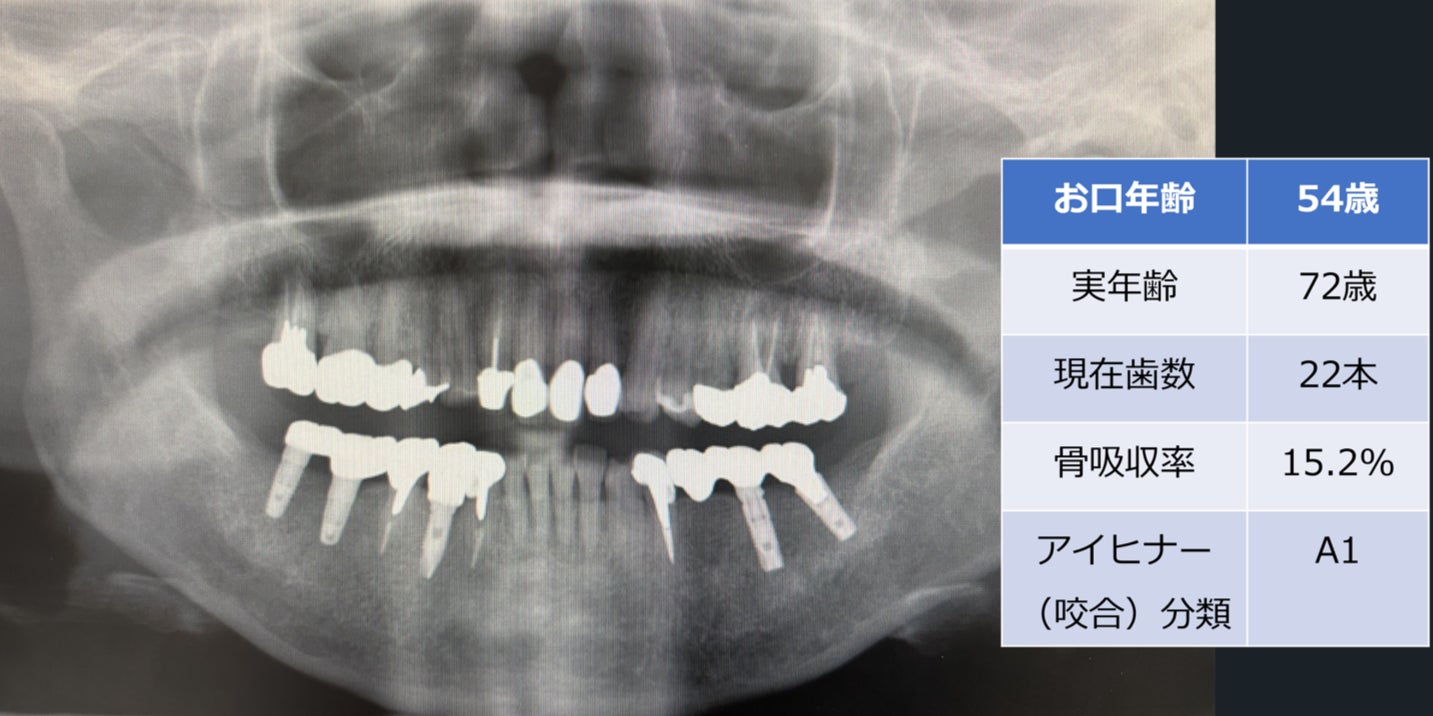

「お口年齢AI」は、歯科エックス線画像を活用して患者の口腔内の状態を分析し、実年齢に対する口腔の健康状態を示すシステムです。

このAIは、エックス線画像から得られるデータを基に、歯や骨の状態を評価し、口腔年齢を算出します。